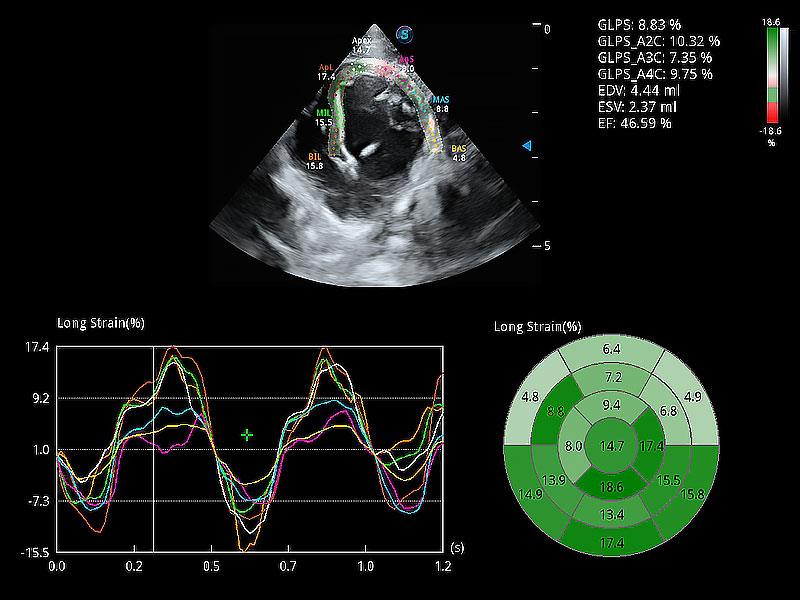

通過心肌識(shí)別技術(shù)與二維斑點(diǎn)追蹤技術(shù)相結(jié)合,對(duì)心臟的超聲圖像進(jìn)行量化分析。計(jì)算心肌17個(gè)節(jié)段的應(yīng)變、應(yīng)變率、速度、位移等,并通過牛眼圖的形式進(jìn)行呈現(xiàn)。